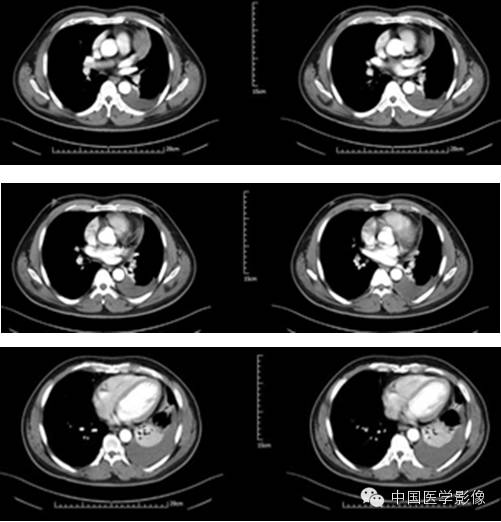

病例1【病史】

患者男,50岁。

患者因“突发胸痛4余天”入院。患者无发热、盗汗,无声音嘶哑,无咳痰,无面部及双下肢肿胀。门诊以“左前上纵膈肿瘤”收入院。患者自发病以来,饮食睡眠可,大小便正常,体重较前无明显减轻。既往高血压病史1年,否认其他传染病史。

专科查体:胸廓对称,双侧呼吸动度均等,胸壁无明显压痛及肿块,双侧语颤正常,双肺叩清音,左下肺呼吸音低,右肺呼吸音可,双肺未闻及干湿啰音。

入院诊断:左前上纵膈肿瘤:畸胎瘤?

【影像资料】

平扫

动脉期

静脉期

延迟期

【病理结果】

孤立性纤维性肿瘤